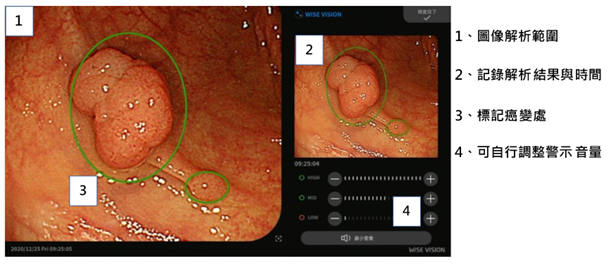

受惠于臺湾全民健保所建立的庞大数据數據库,医疗影像判读也被视为臺湾发展医疗AI最适合切入、临床阻力较小的应用。在众多医疗新创业者、资通讯厂商大举投入之际,臺湾目前却仅有3项AI医材产品成功取得臺湾FDA (TFDA)认证(业者为爱因斯坦、宏碁智医与晋弘科技),显见臺湾医疗AI发展仍处于初期临床验证、产学研合作阶段。

当医疗影像AI产品效能可达高水准的灵敏度、特异度(specificity)后,仍须挑战实际应用于临床或推广到医疗体系内,此有待市场考验。医疗AI整合平臺可望扮演关键角色,担任医疗AI軟件供应商与使用者间的桥梁,相关业者/平臺包括医疗AI软硬件整合商、传统医疗设备厂建置的AI平臺。